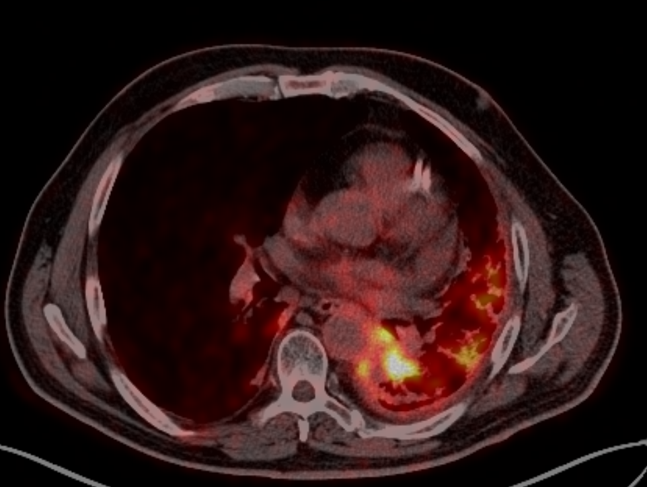

Заключение ПЭТ-КТ с ФДГ от 29.03.2022г:

- картина центральной опухоли левого легкого с признаками обструктивного пневмонита, мтс с поражением ипсилатеральных и подкаринальных лимфоузлов.

В воротах левого легкого определяется метаболически активный опухолевый узел с вовлечением главного, нижнедолевого, частично верхнедолевого бронхов, общими наибольшим размерами около 83 мм в аксиальной проекции и до 81 мм в краниокаудальной проекции, SUVmax=21.41. Опухоль располагается на расстоянии около 30 мм от киля трахеи с вовлечением левой легочной артерии (обхват около 50%) и тесным прилеганием к нисходящей аорте. Окружающая паренхима левого легкого с признаками воспаления. В правом легком очаговая и инфильтративная патология легких не определяется.Определяются метаболически активные медиастинальные лимфоузлы, наибольшими размерами/накоплением РФП: подкаринальной группы (7) до 10 мм, SUVmax=7.49; субаортальной группы (5) до 8 мм, SUVmax=4.70. Лимфоузлы ворот левого легкого четко не дифференцируются, вероятнее сливаются с основной опухолевой массой.

В воротах левого легкого определяется метаболически активный опухолевый узел с вовлечением главного, нижнедолевого, частично верхнедолевого бронхов, общими наибольшим размерами около 83 мм в аксиальной проекции и до 81 мм в краниокаудальной проекции, SUVmax=21.41. Опухоль располагается на расстоянии около 30 мм от киля трахеи с вовлечением левой легочной артерии (обхват около 50%) и тесным прилеганием к нисходящей аорте. Окружающая паренхима левого легкого с признаками воспаления. В правом легком очаговая и инфильтративная патология легких не определяется.Определяются метаболически активные медиастинальные лимфоузлы, наибольшими размерами/накоплением РФП: подкаринальной группы (7) до 10 мм, SUVmax=7.49; субаортальной группы (5) до 8 мм, SUVmax=4.70. Лимфоузлы ворот левого легкого четко не дифференцируются, вероятнее сливаются с основной опухолевой массой.